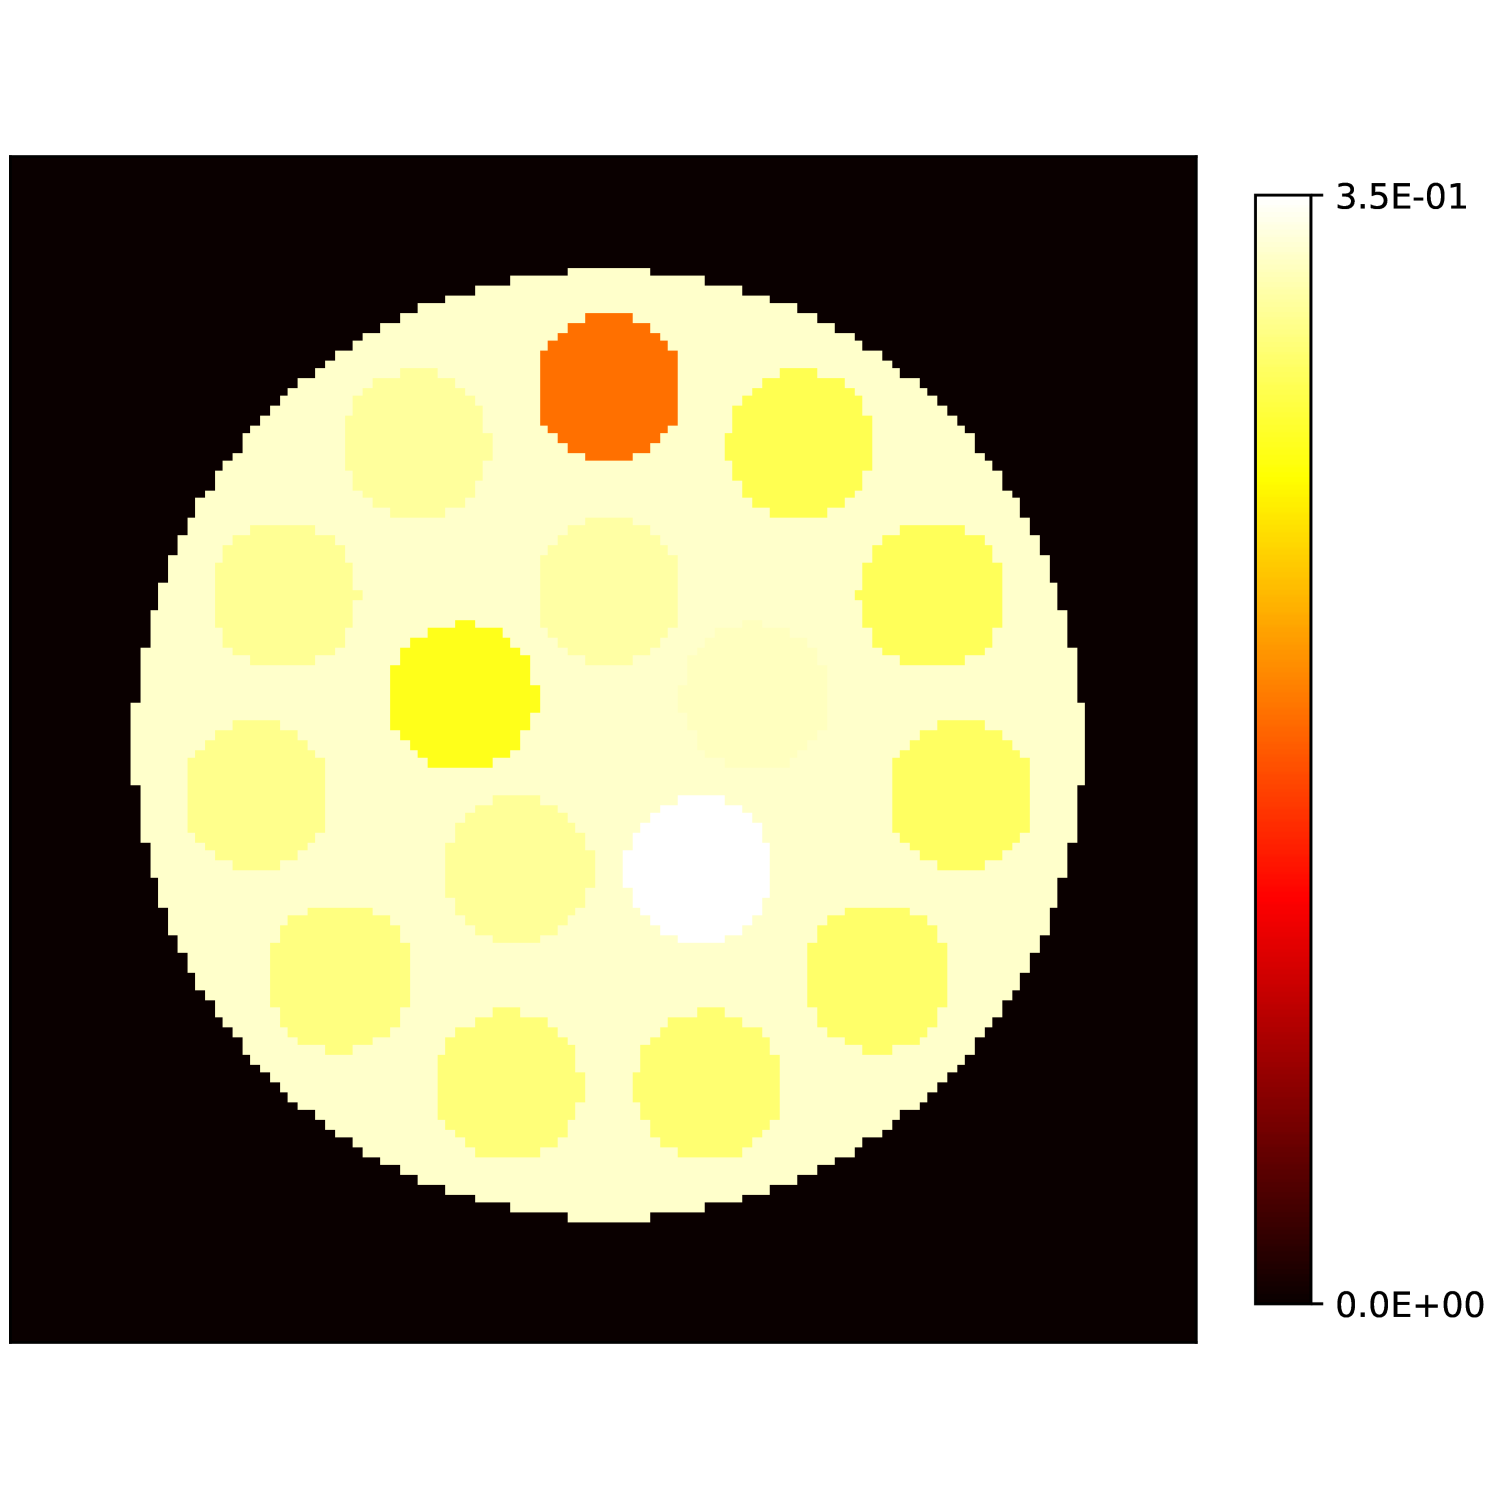

Our theoretical results show that generic concentrations and maps can be recovered exactly even when the fieldmap is not identifiable. To illustrate the impact of this fact, we perform a recovery experiment on a water (Fig. 2(a)), fat (Fig. 2(b)) and silicone (Fig. 2(c)) in silico phantom. The concentrations are all real. The values for the fieldmap and used to generate the signal are shown in Figs. 2(d) and 2(e). The echo times have the form where ms and ms with .

We solve (23) using projected gradient descent as initial iterate a vector with all components equal to one. Forward finite-differences were used to compute the gradient. The bound on the norm of the gradient is Hz at voxels with non-zero signal magnitude, and kHz at voxels with zero signal magnitude. This avoids imposing artificial constraints at voxels with no signal. The step size used is and the termination conditions

In Figs. 2(f), 2(g) and 2(h) show the recovered concentrations of water, fat and silicone, and Fig. 2(j) shows the recovered . These recovered quantities are all qualitatively similar to their true values. In contrast, Fig. 2(i) shows the recovered fieldmap, which differs from its true value. By comparing the errors in the recovered concentrations, we see that they are within a reasonable accuracy except in regions with a large magnitude for the fieldmap gradient, indicating a bound that is too small (Figs. 2(k), 2(l) and 2(m)). A similar behavior is seen in the recovered (Fig. 2(o)). The error for the recovered fieldmap tends to be larger outside the area of the phantom (Fig. 2(n)).